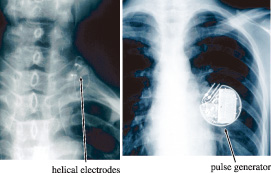

図 5 VNS装着後のX線像

刺激発生装置,らせん状電極,リード線が所定の

位置に埋め込まれている |